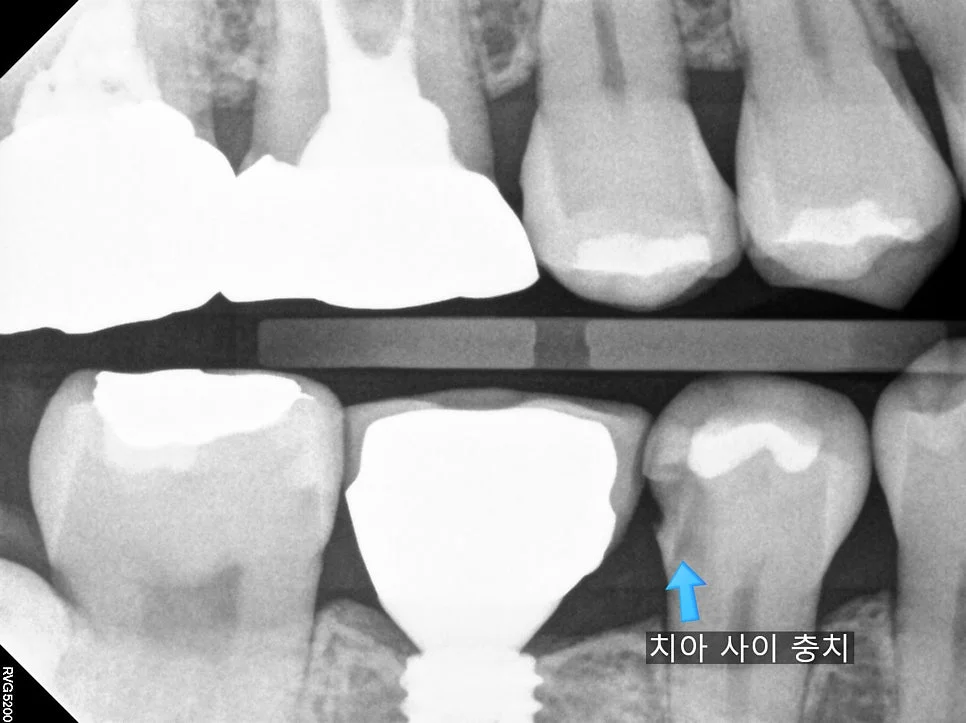

이렇게 틈이 벌어지면 음식물이 많이 끼게 되고 그 과정에서 충치가 생기는 경우가 흔한데요. 교익 방사선(Bitewing X-ray) 사진 촬영을 통해 치아 사이 충치를 확인해 보았는데요!

교익 방사선 사진 — 화살표로 치아 사이 충치(검은 음영) 위치 표시

방사선 사진상에서 치아가 있어야 할 위치에 검은 음영이 있다면 충치로 진단을 하는데 딱 그 자리에 충치가 있는 모습을 볼 수 있습니다ㅃ

해당 치아의 충치를 치료하고 음식물이 끼지 않게 하기 위해 임플란트와 긴밀한 틈(빡빡하게)을 만들어 주는 ‘인레이’ 치료를 계획합니다!